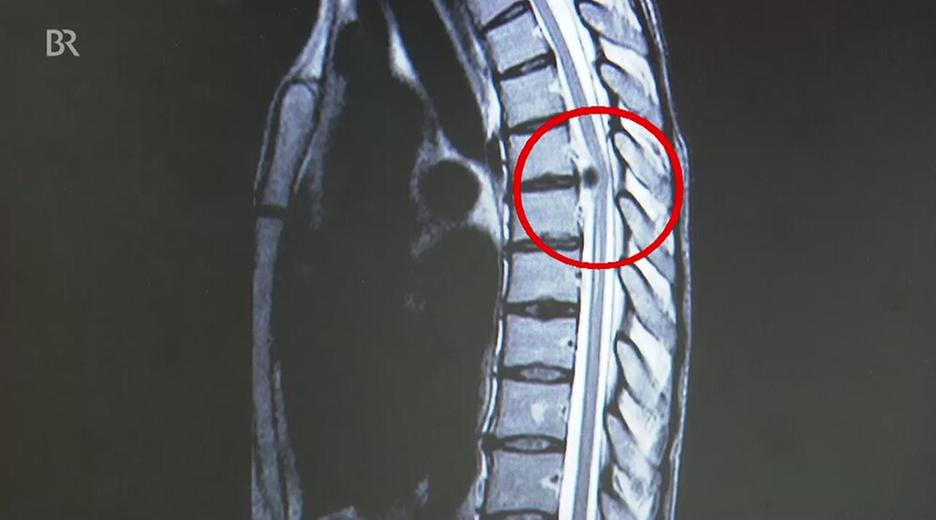

Die Themen der Sendung:Übergewicht bei Kindern: Die Ernährung in den ersten 1.000 Tagen ist entscheidend.Weltweit gibt es immer mehr übergewichtige Kinder. Laut dem Robert Koch Institut gelten hierzulande fast 15 Prozent der Kinder und Jugendlichen als zu dick. Experten gehen davon aus, dass die Anlagen für die Neigung zum Übergewicht schon sehr früh gelegt werden. Konkret: bereits im Mutterleib und in den ersten Lebensjahren. Lebensstil und die richtige Ernährung von Mutter und Kind spielen demnach eine gewichtige Rolle. Doch auch in der weiteren Entwicklung kann man aktiv gegensteuern. "Gesundheit!" stellt spezielle Angebote für Eltern und Schulen vor, die dabei helfen, Kinder gesund durch den Alltag zu bringen. Bandscheibenschäden der Brustwirbelsäule: Warum sie oft lange nicht erkannt werdenDiese Symptome können auf ganz verschiedene Krankheiten hindeuten: Schmerzen im Brustbereich oder entlang der Rippen, beim Bewegen der Arme, beim Husten und Lachen, Gefühlsstörungen oder sogar Lähmungserscheinungen. Steckt eine Borreliose, Gürtelrose, Lungenerkrankung oder ein Tumor hinter diesen Beschwerden? Der Weg zur Diagnose „Bandscheibenvorfall an der Brustwirbelsäule“ ist oft eine Odyssee. "Gesundheit!" zeigt, in welchen Fällen dann eine konservative Behandlung genügt, und warum eine Operation an der Brustwirbelsäule besonders heikel ist.Erythrophobie: Angst vor dem ErrötenOft passiert es ausgerechnet in Situationen, in denen es am wenigsten passt: bei einer Präsentation im Beruf, beim Gespräch mit dem Chef, bei einer Prüfung oder einem Date. Das Blut steigt in den Kopf, das Gesicht wird warm, die Gedanken kreisen nur noch um die glühenden Wangen. Rotwerden ist unangenehm, doch manche Menschen entwickeln eine regelrechte Panik davor. Wenn man aus Angst vor dem Erröten andere Menschen meidet oder nicht mehr aus dem Haus geht, ist die Schwelle zur Erkrankung überschritten. Erythrophobie heißt die Angst vor dem Erröten. "Gesundheit!" hat die 17-jährige Svenja getroffen, bei der die Angststörung so schlimm war, dass sie nach ihrem Schulabschluss sogar den Kontakt zu Freunden abgebrochen hat. Haare: Was verraten sie über unsere Gesundheit?Rund drei Millionen Euro geben die Deutschen jährlich für Haarpflege aus. Tendenz steigend. Schöne, gesunde Haare sind den meisten ziemlich wichtig. Ob unkomplizierter Kurzhaarschnitt oder Lockenmähne, ob praktisch oder aufwendig frisiert – unser Kopfschmuck sagt viel über unsere Persönlichkeit aus. Aber was verraten die Haare über unsere Gesundheit? Speichern sie die Umwelt- und Lebensbedingungen? Diesen Fragen geht der Reporter Fero Andersen nach – bei einem Friseur, einer Dermatologin und einer Kriminalbiologin.